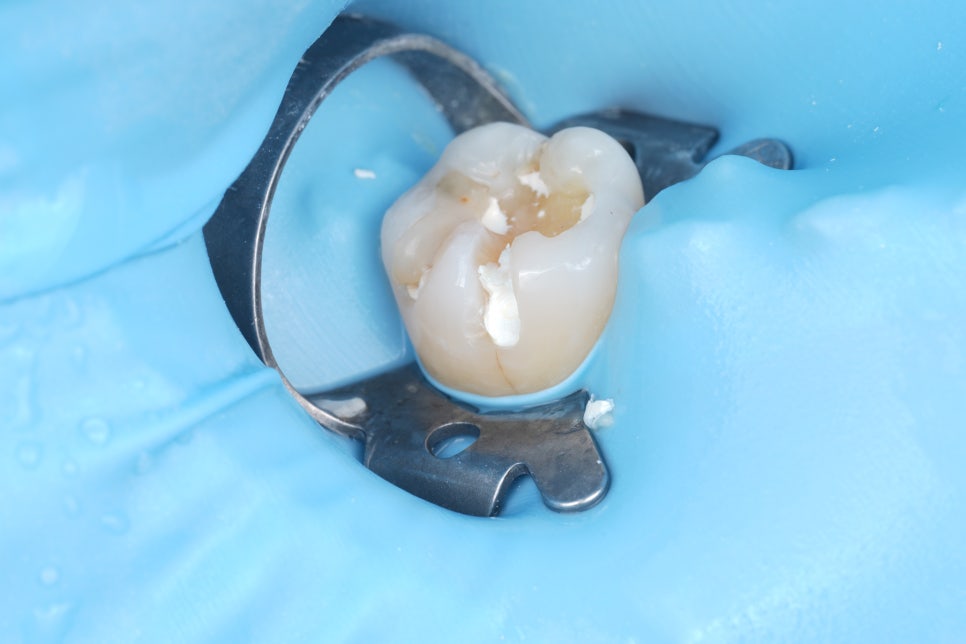

러버댐을 장착하고 수분이 닿지 않도록 격리한 다음, 한 층씩 빛으로 굳히면서 양옆 치아와 자연스럽게 어울리도록 형태를 잡아줘야 해요.

촬영일 : 250909

어금니도 충치 제거 후 자연스레 쌓아 올렸어요.

촬영일 : 250909 / 250909